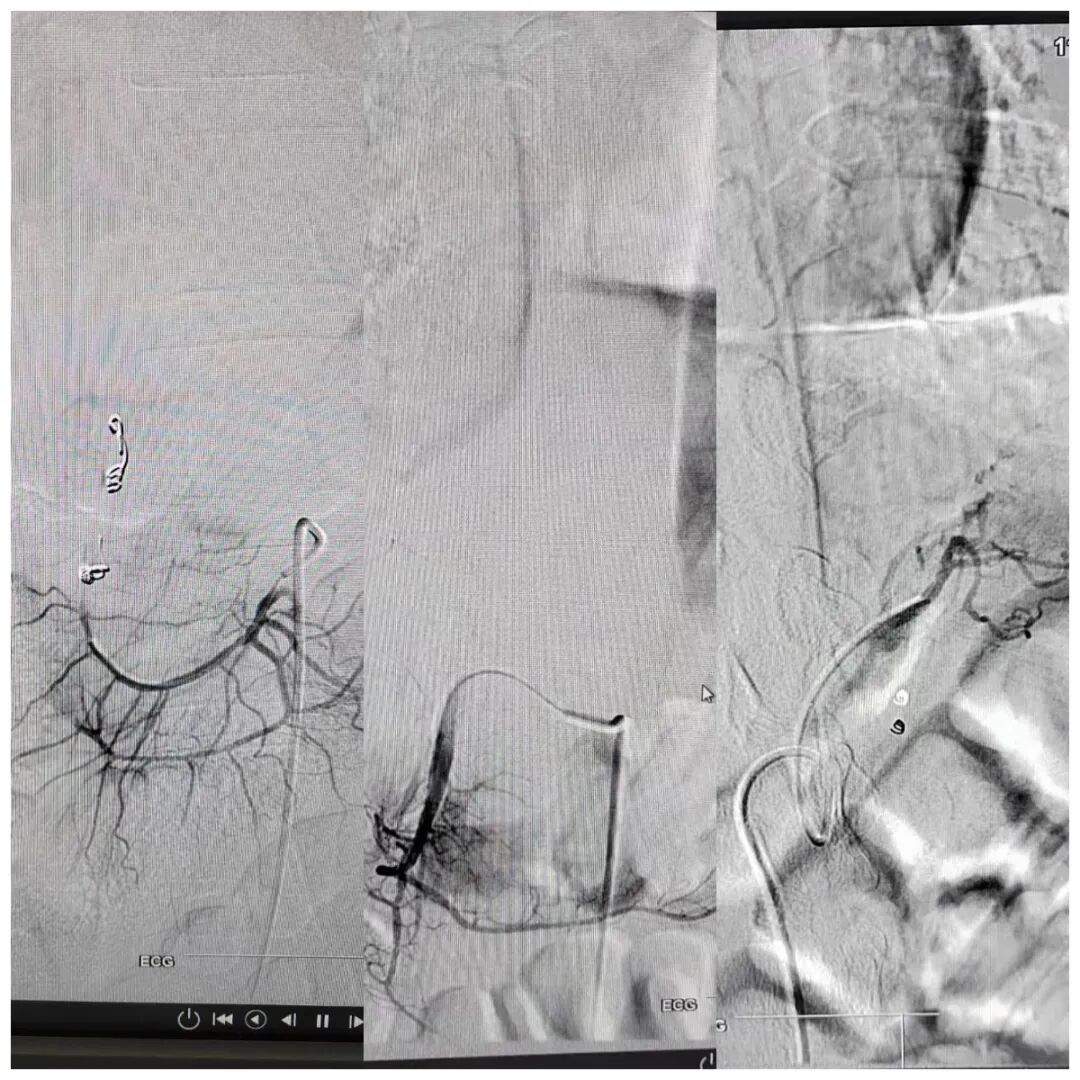

面对这样的情况,时间就是生命!修文百信医院会诊专家组立即制定

出完整的治疗方案:急诊行介入止血治疗。

经过整晚的不懈努力,抗争在死亡的边缘,该患者的血止住了!!患者生

命体征也逐渐平稳了下来,手术完美结束!

这就是介入治疗的魅力!不但挽救了一条鲜活的生命,对患者还没有

任何创伤,就是一个“小小的针眼”经过几天恢复也不会留下任何痕迹!

图片来源:介入肿瘤科